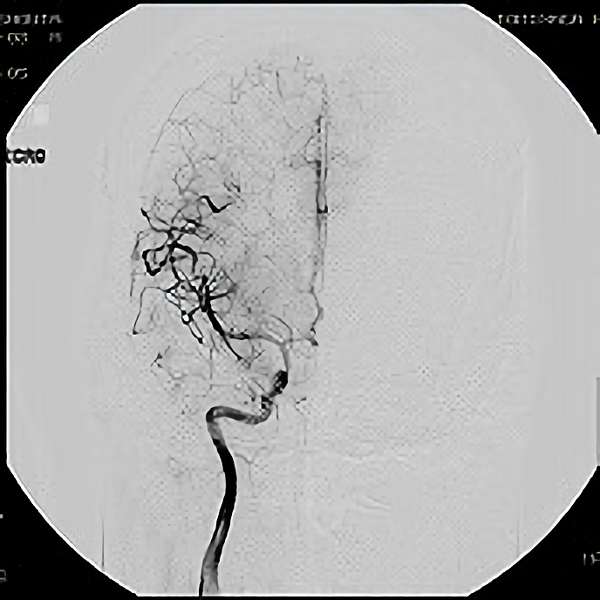

脳血管撮影

手術前

手術後